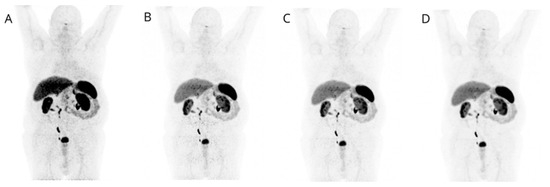

The only significantly different (p < 0.001) parameters between β1600 and STD (p < 0.001) were signal-to noise liver ratio (SNR-L) (β1600 vs. STD: mean = 9.9 vs. 7.3; median = 9.9 vs. 7.1; range: 4.7–15.7 vs. 4.6–14.0) and standard deviation of the liver background (β1600 vs. STD: mean = 0.5 vs. 0.7; median =0.5 vs. 0.7; range: 0.2–1.1 vs. 0.3–1.3) (Figure 3).

Figure 3.

(a) Standard deviation of the liver background of β1600 (red) and STD (blue) are significantly different p < 0.001; (b) Signal-to-noise liver ratio of β1600 (red) and STD (blue) are significantly different at p < 0.001.